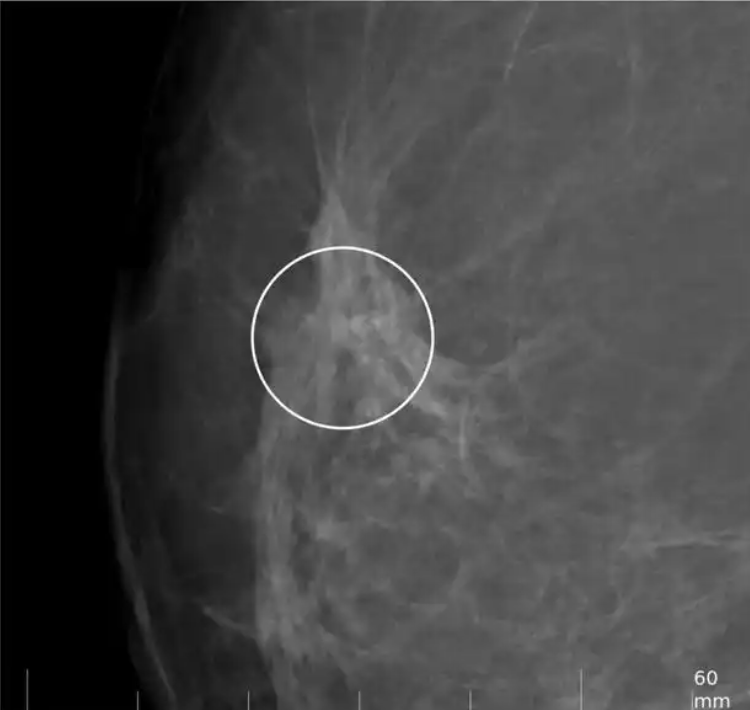

通過深度學(xué)習(xí)技術(shù)對X光、CT、MRI、超聲波等醫(yī)學(xué)影像進(jìn)行自動分析,幫助醫(yī)生快速準(zhǔn)確地識別病變區(qū)域。